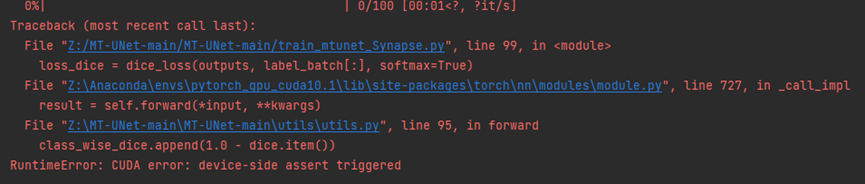

转化出来的nii.gz中的维度512512203是正确的,挺高兴的,但是当我将数据集经过预处理以后,放入模型中,进行训练的时候,出现了问题。

经过查阅资料发现,是由于num_class, 即训练中分类的数量少于label数据中的标签数量导致的。通过增加num_class的值,知道256才可以进行训练,说明label数据中的标签数量为256个,分为了256类,这明显不对的,我们只有两类。但是为什么会这么多呢?返回头去看.nii.gz的信息,可以看到原始数据的label中image value range为[0,13],包含0-13,14个数据。而我们的image value range为[0,255],包含0-255,256个数据。因此推测,这14和256就是label数据中标签的数量。虽然我们用png转化的.nii.gz只有0和255两个值,但是范围仍是[0,255].